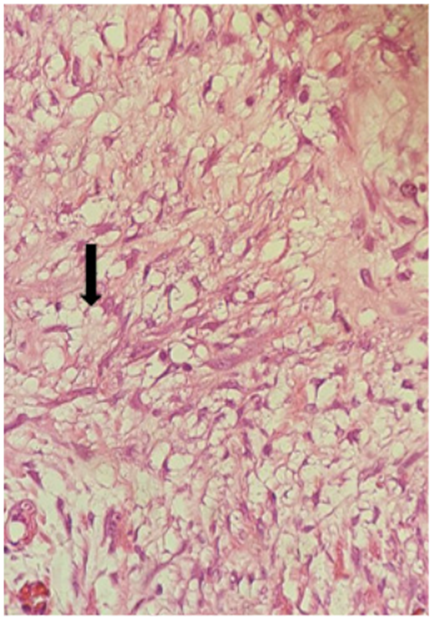

Posteriormente se decidió una nueva intervención quirúrgica y se realizó laparotomía exploratoria, identificando un asa de intestino delgado con zona de estenosis aproximadamente a 150 cm de la válvula ileocecal (Figura 3), que se trató mediante resección intestinal mas anastomosis. El examen histopatológico reveló mesenteritis esclerosante. A nivel de la subserosa y meso del intestino delgado, se observó una marcada proliferación en sábanas de fibroblastos fusiformes y estrellados (Figura 4). También se observaron macrófagos cargados de lípidos junto a áreas hipercelulares con mitosis frecuentes y zonas de colágeno gruesos en medio de los fibroblastos, edema estromal e inflamación linfoplasmocitaria (Figura 5).

Es un trastorno fibro-inflamatorio, de etiología desconocida, que afecta principalmente al mesenterio del intestino delgado 5,6,7. Se describen diferentes tipos histológicos en relación a la evolución de la enfermedad: lipodistrofia mesentérica con predominio de macrófagos espumosos cargados de lípidos, paniculitis mesentérica en donde existe un predominio de células plasmáticas y linfocitos, y la mesenteritis retráctil, la fase final, en donde predomina la fibrosis por el depósito de colágeno 7.